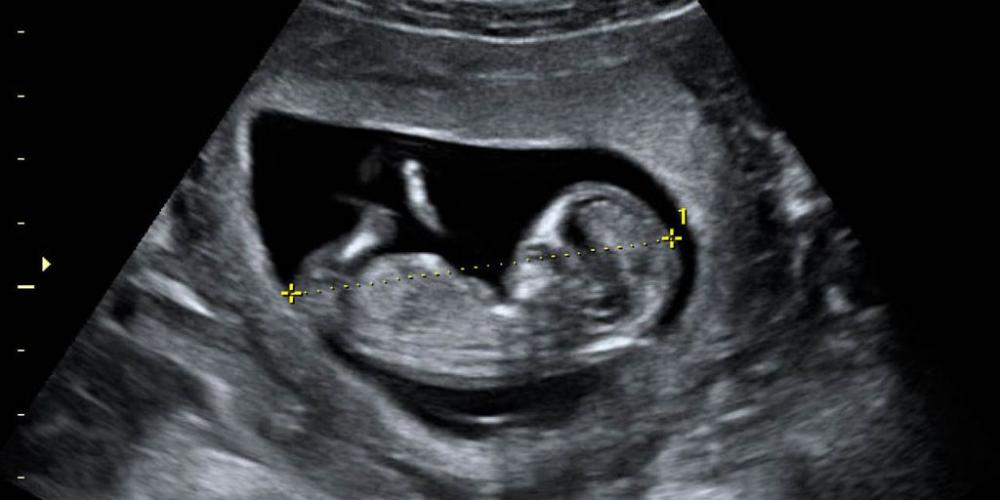

Cada fin de año, todos tienden a hacer una evaluación, aunque fuera ligera, sobre los últimos 12 meses, además de pensar en los desafíos para el nuevo año. En lo referente a la protección de la vida más...